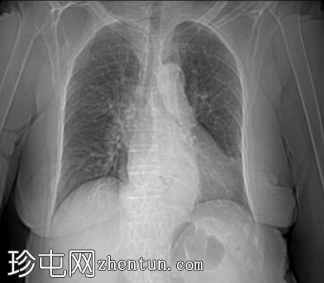

3.jpg

C+ CTPA

CTPA显示:

双侧肺动脉主干均可见大片充盈缺损,右侧上、下主干及左侧下叶主干可见闭塞

心脏增大

由于食管裂孔扩大,胃位于后纵隔,无胃扭转征象